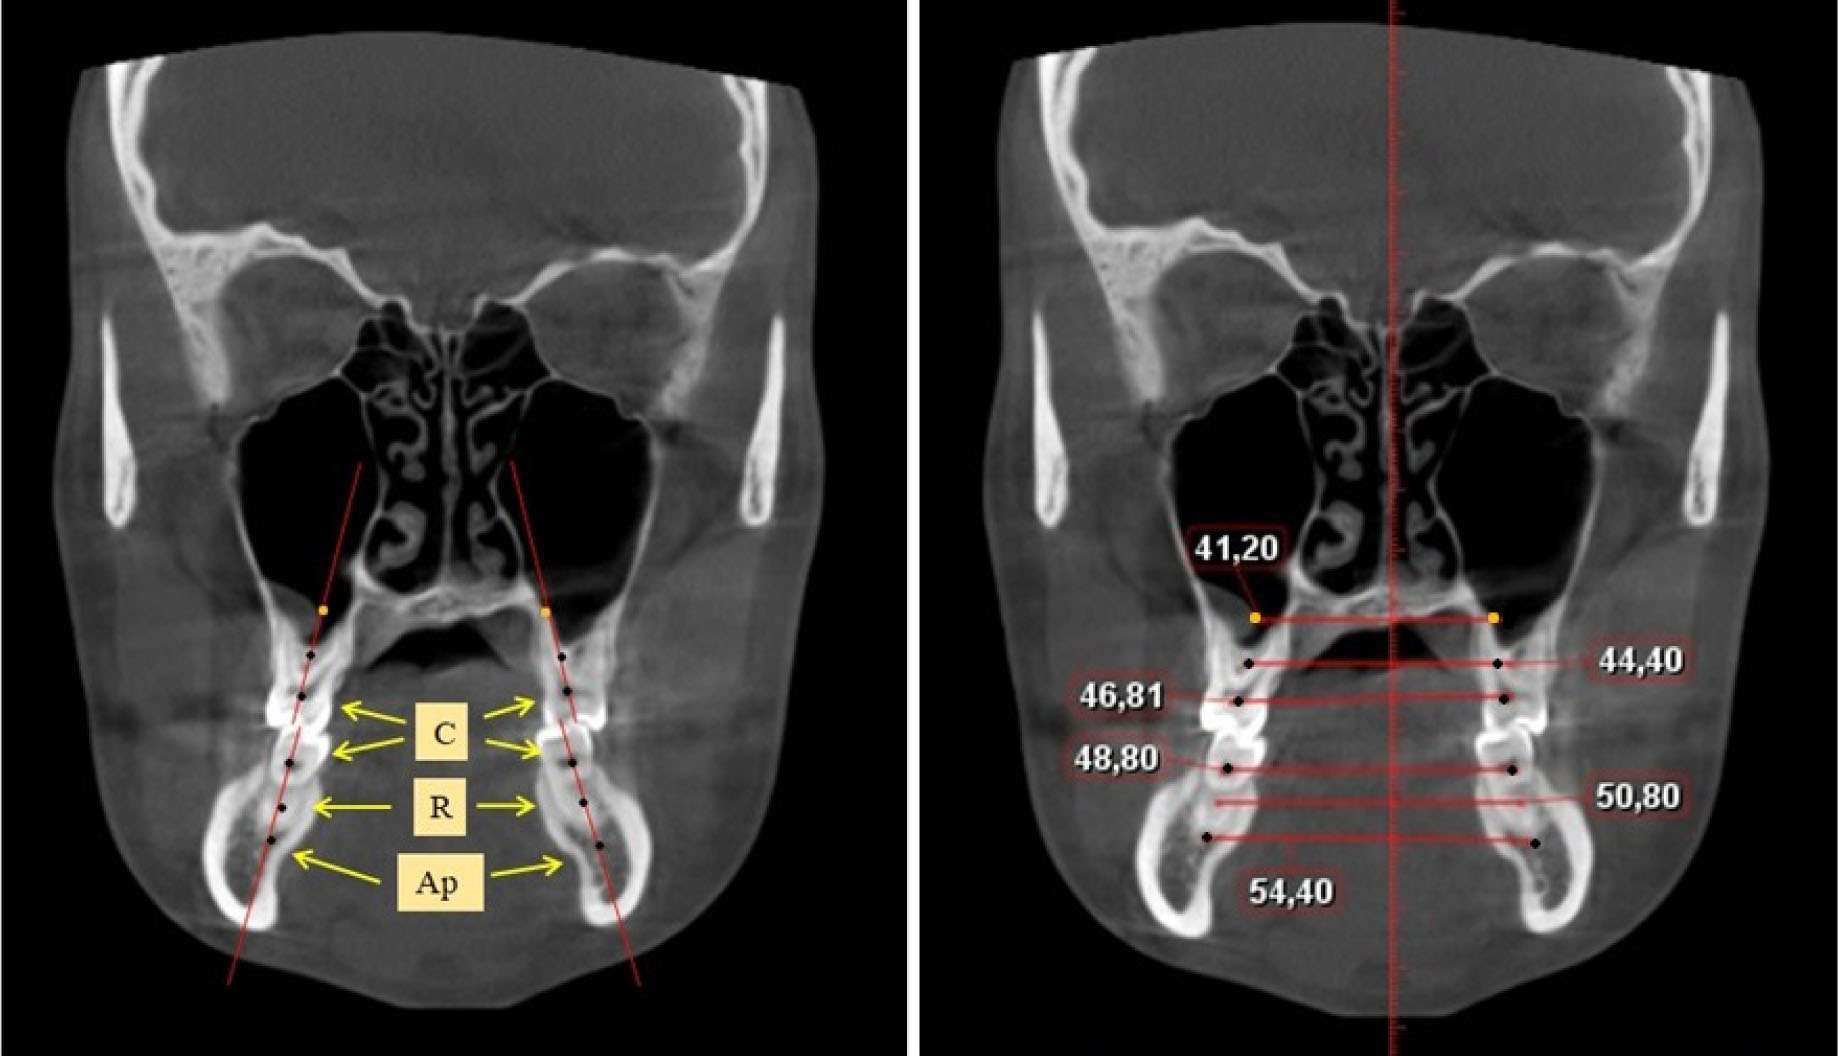

Состояние окклюзии оценивали на объемном снимке черепа, а положение передних зубов – в сагиттальной проекции (рис. 1).

Рис. 1. Объемный снимок головы и определение межрезцового угла в сагиттальной проекции

Межрезцовый угол измеряли между условными срединными вертикалями медиальных резцов, что позволяло определять трузионный тип зубо-челюстных дуг.

Ширину лица измеряли как непосредственно на пациенте между трагиональными точками верхней части козелка, так и на КЛКТ между суставными головками. Измерение ширины лица позволяло определить его соразмерность с шириной альвеолярных дуг обеих челюстей.

Определение ширины задних отделов зубочелюстных дуг проводили на срезах КЛКТ через дистальные поверхности вторых моляров. Проводили условные срединные вертикали вторых моляров, на которых устанавливали точки на уровне шеек зубов («С»), на уровне середины корня («R») и на уровне апикальной части корня («Ар»), как на верхней, так и нижней челюсти (рис. 2).

Рассчитывали коэффициент соотношения ширины лица с размерами альвеолярных дуг между цервикальными точками вторых верхних моляров (фациально-цервикальный коэффициент).

Ширина альвеолярных дуг на КЛКТ на уровне шеек дистальной стороны вторых моляров на верхней челюсти была в среднем по группе (53,12 ± 1,14) мм. Таким образом, в целом по группе, фациально-цервикальный коэффициент составил (2,66 ± 0,02), что позволяло данную величину использовать как эталон ширины заднего отдела арок. Ширина альвеолярных дуг на КЛКТ на уровне шеек дистальной стороны вторых моляров на нижней челюсти была (54,16 ± 1,23) мм. Превышение размера в (1,02 ± 0,01) раза может быть использовано в качестве расчетного показателя для определения оптимальной ширины альвеолярного гребня нижней челюсти без атрофии ее альвеолярной части.

Ширина альвеолярных дуг на уровне середины корня вторых моляров верхней челюсти была в среднем по группе (50,11 ± 0,83) мм. Таким образом, различия в размерах в меньшую сторону составили (3,01 ± 0,03) мм. Таким образом, различия в размерах между расчетной и фактической в пределах 3 мм была характерны для атрофии альвеолярного отростка до уровня середины корня, что можно определять как атрофию 2-й степени.

Ширина альвеолярных дуг на уровне середины корня вторых моляров нижней челюсти была в среднем по группе (57,44 ± 1,37) мм. Таким образом, различия в размерах в большую сторону составили (3,26 ± 0,05) мм. Таким образом, различие в размерах между расчетной и фактической в пределах 3 мм было характерно для атрофии альвеолярной части до уровня середины корня, что можно определять как атрофию 2-й степени.

Ширина альвеолярных дуг на уровне апикальной части корня вторых моляров верхней челюсти была в среднем по группе (47,02 ± 0,93) мм. Различия в размерах (по сравнению с расчетной величиной) в меньшую сторону составили (6,1 ± 0,07) мм. Таким образом, разница в размерах между расчетной и фактической величиной более 6 мм была характерна для полной атрофии альвеолярного отростка до уровня середины корня, что можно определять как атрофию 3-й степени.

Ширина альвеолярных дуг на уровне апикальной части корня вторых моляров нижней челюсти была в среднем по группе (60,14 ± 1,22) мм. Различия в размерах (по сравнению с расчетной величиной) в меньшую сторону составили (5,96 ± 1,07) мм. Таким образом, разница в размерах между расчетной и фактической величиной более 6 мм была характерна для полной атрофии альвеолярного отростка до уровня середины корня, что можно определять как атрофию 3-й степени.